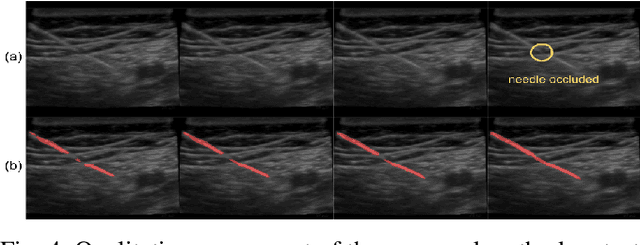

Abstract:Segmenting a moving needle in ultrasound images is challenging due to the presence of artifacts, noise, and needle occlusion. This task becomes even more demanding in scenarios where data availability is limited. Convolutional Neural Networks (CNNs) have been successful in many computer vision applications, but struggle to accurately segment needles without considering their motion. In this paper, we present a novel approach for needle segmentation that combines classical Kalman Filter (KF) techniques with data-driven learning, incorporating both needle features and needle motion. Our method offers two key contributions. First, we propose a compatible framework that seamlessly integrates into commonly used encoder-decoder style architectures. Second, we demonstrate superior performance compared to recent state-of-the-art needle segmentation models using our novel convolutional neural network (CNN) based KF-inspired block, achieving a 15\% reduction in pixel-wise needle tip error and an 8\% reduction in length error. Third, to our knowledge we are the first to implement a learnable filter to incorporate non-linear needle motion for improving needle segmentation.